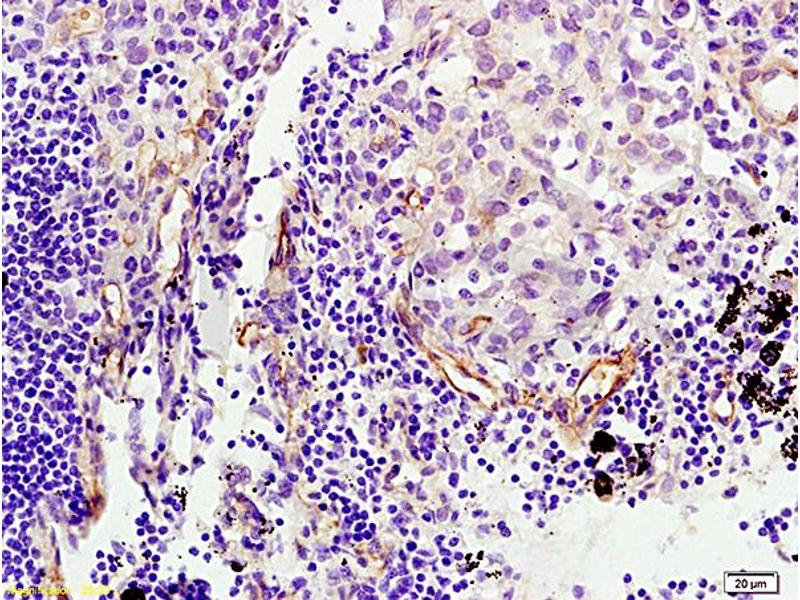

Découvrez des anticorps Endoglin fiables issus d’une large sélection de fabricants renommés. Notre portefeuille permet une détection précise de Endoglin dans plusieurs espèces, y compris Human, Mouse, Rat, Pig, Dog, Horse, Monkey, Cynomolgus, Primate, Rhesus Monkey, Guinea Pig, Rabbit, et prend en charge diverses applications de recherche telles que FACS, WB, IHC, ELISA, IF.